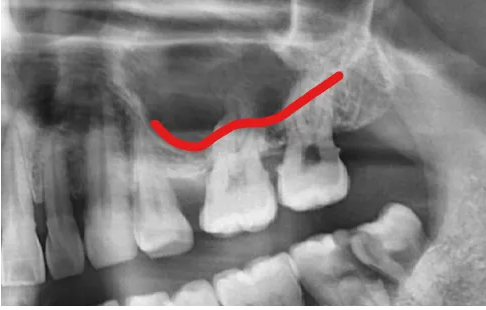

2024.02.13 초진 파노라마, (사진상 좌.우 반대)

- 충치 문제: 오른쪽 어금니(사진상 왼쪽)는 뿌리까지 충치가 심해 발치가 필요한 상태였습니다.

- 잇몸뼈 부족: 왼쪽 위 어금니(사진상 오른쪽)는 이 뽑은 후 잇몸뼈가 1~2mm밖에 남지 않을 것으로 예상되었는데요.

이 경우 임플란트 고정이 어렵기 때문에 뼈 이식과 상악동 거상술이 필요했습니다.

- 교합 불안정: 치아가 빠진 자리를 오랫동안 방치해 배열이 틀어지면서 치아 맞물림 상태가 매우 불안정해졌습니다.

상악동 구조 파악을 위한 CT

또한 왼쪽 위 어금니는 발치 후 잇몸뼈가 부족뿐만 아니라, 상악동이라는 공기주머니와 가까운 위치에 있어 측면 접근법 상악동 거상술이라는 난도 높은 수술과 임플란트 골이식이 필요했는데요.

빨간선이 상악동 위치

상악동 위치

수술 후 엑스레이에서 상악동이 인공 뼈로 채워진 모습이 확인되었고, 임플란트가 안정적으로 자리 잡았습니다.